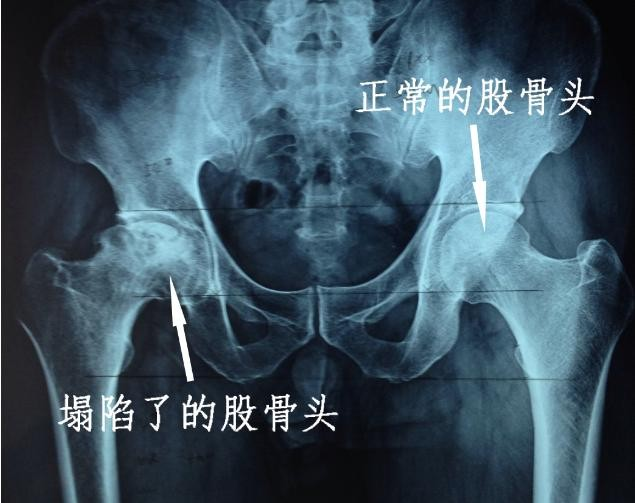

在正常人的骨骼结构中,股骨头是连接髋关节和骨盆的关键部分,它起到支撑身体的重要作用。

然而,阳鸣村的居民却缺少了这一关键部位,导致了他们的骨骼发育异常。

此外,四肢的延展性软骨也出现了损坏,骨骼发育受到了严重影响。